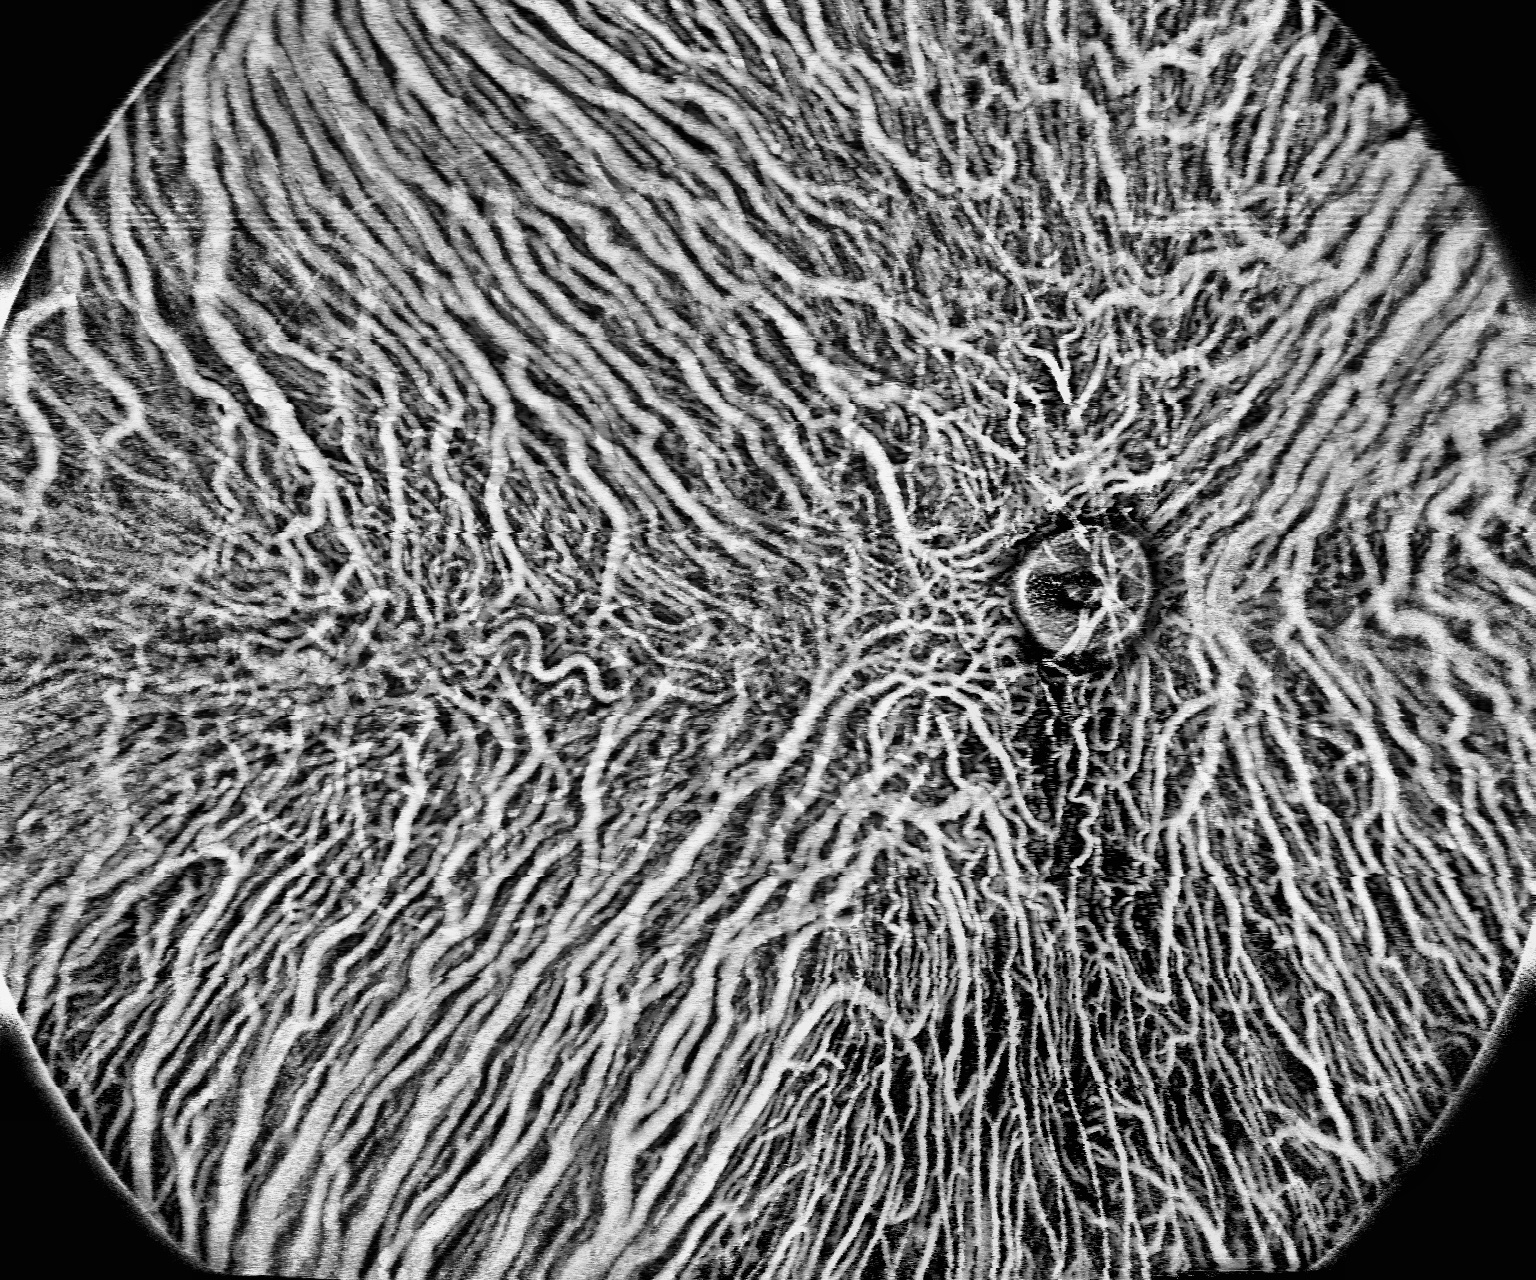

Choroid OCT-A

- Unieke kwantificatie functies voor Choroid OCT-A

- Choroid Vessel Index (3D-CVI)

- Choroid Vessel Density (2D)

- Choroid Vessel Voilume ratio (CVV/a)

- Choroidal Stroma Index (CSI)

- Choroidal Stroma Volume ratio (CSV/a)